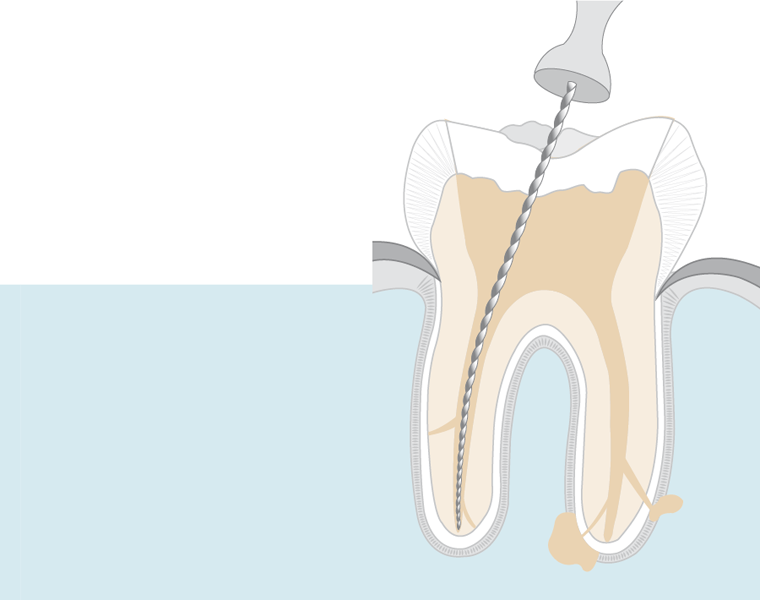

- Pulpektomija: Napravi se otvor u kruni zuba. Bolesna ili mrtva pulpa se uklanja iz pulpne komore i korijenskih kanala.

- Čišćenje i oblikovanje: Male turpije se koriste za čišćenje, proširenje i oblikovanje kanala kako bi se pripremili za punjenje.

- Punjenje: Izdubljeni kanali ispunjeni su biokompatibilnim materijalom, obično tvari sličnoj gumi koja se naziva gutaperka, i zapečaćeni adhezivnim cementom.